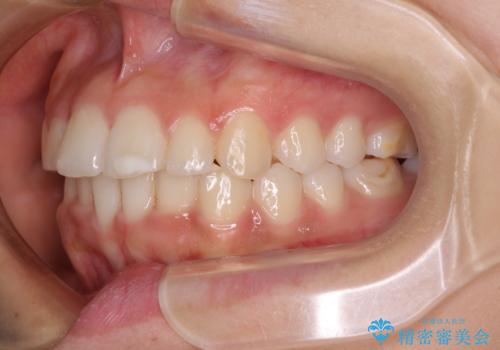

大きなトラブルもなく、順調に歯列が整ったため、僅か9ヶ月で装置を外すことができました。

あまりに短期間であったため、患者様自身も非常に驚いていらっしゃいました。